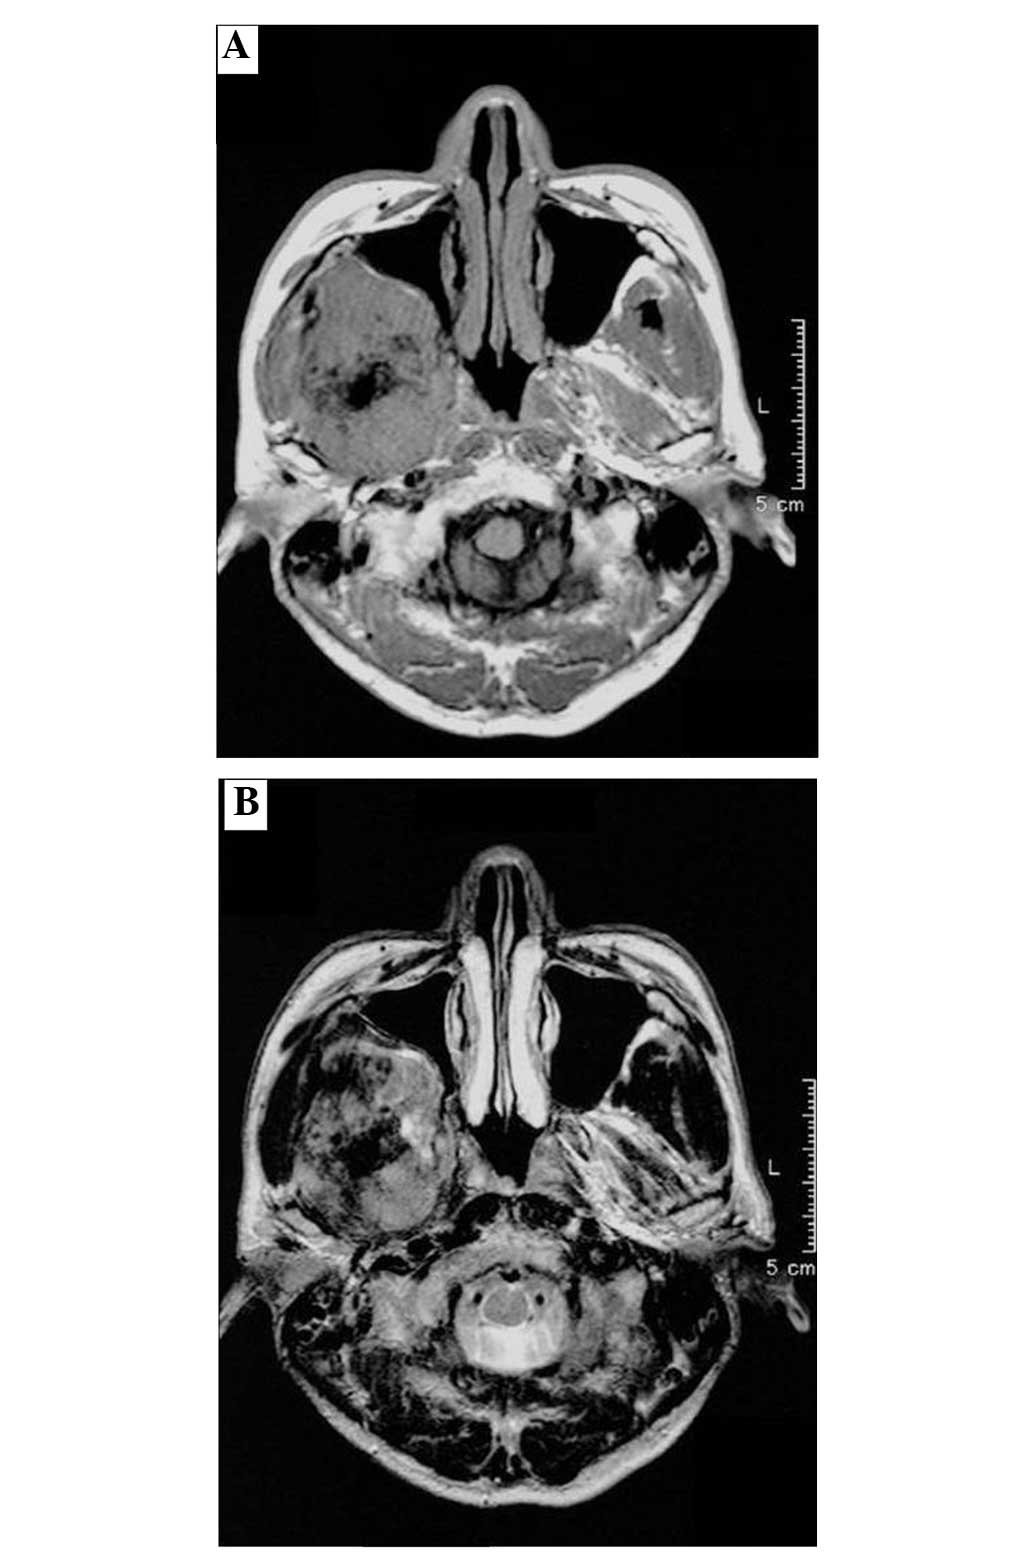

Figure 2

Low-intensity within an isointensity mass on an axial view of magnetic resonance imaging showing ossification in the tumor on (A) T1- and (B) T2-weighted images.

A 56-year-old male presented with a mass in the right facial bone that had been apparent for three months, and dysesthesia, which had occurred gradually at this site. The patient incidentally identified the tumor and visited Wakakusa-Daiichi Hospital, Higashi-Osaka (Osaka, Japan), where the mass was confirmed with computed tomography (CT) examination. Nothing of note was found in the patient’s past medical and family histories, and the findings from the routine laboratory studies were within the normal limits. Plain X-rays showed no particular findings, but regional CT showed a soft-tissue mass with prominent ossification in the central region, and involving the parapharyngeal space (Fig. 1), in which the anterior septum ballooned owing to compression from the mass. Magnetic resonance imaging (MRI) revealed heterogeneously low intensity to isointensity results on T1-weighted sequences and low to moderately high intensity results on T2-weighted images, with a size of 5.6×4.8 cm (Fig. 2). Lung CT revealed multiple small nodules that were suspected to be lung metastases (Fig. 3).

Radiologically, tumor matrix mineralization and aggressive bone destruction are strongly suggestive of osteosarcoma. The present case demonstrated a high-density mass in the central area of the tumor on CT examination. On MRI, an intermediate intensity region was observed T1-weighted images and a heterogeneously high intensity region was observed on T2-weighted images. An ossified region in the central lesion, which was produced by tumor cells, showed a low intensity on each of the T1- and T2-weighted images. There was no discernible bone-forming reaction to indicate an osteosarcoma (7).